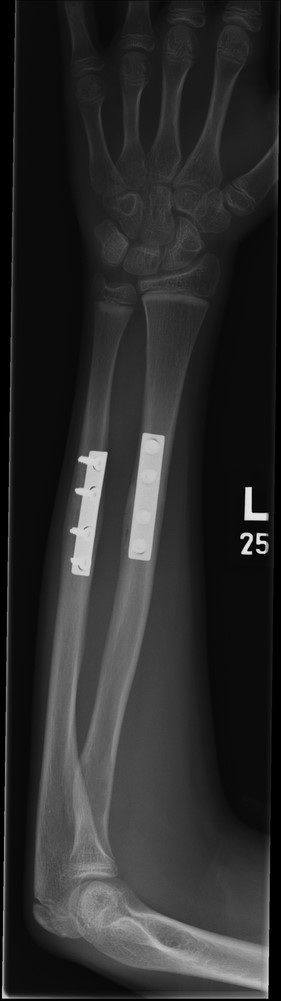

Three months post-operative lateral radiograph showing radiological union.